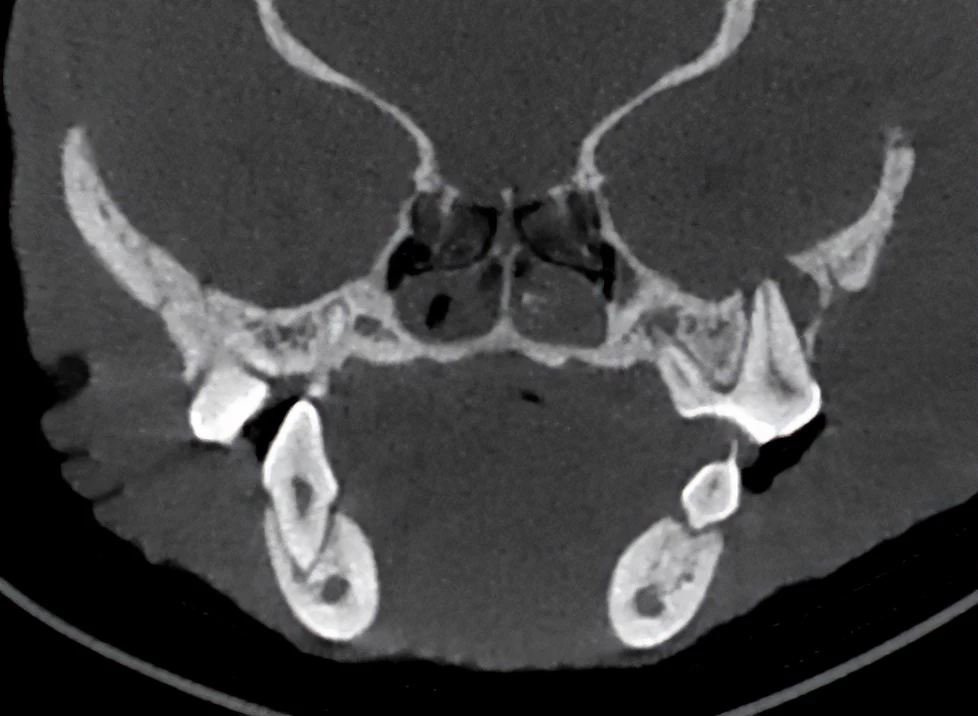

2D image

CBCT image

Une excellente qualité d‘image

Le scanner Planmed Verity ® VET fournit des images 3D très précises de l’anatomie de l’animal, avec une résolution d’ordre submillimétrique. Ce scanner CBCT a été développé pour détecter les pathologies et les fractures même les plus petites dans les structures osseuses de l’animal. Au moyen du scanner CBCT Planmed Verity VET il est possible d’obtenir des images 3D précises des dents, du crâne et des extrémités de l’animal en vue du diagnostic et de la planification du traitement. Bien que les appareils de radiographie numérique et les échographes soient utiles dans le traitement des patients, ces modalités d’imagerie présentent des limitations fondamentales par rapport à l’imagerie 3D, car elles fournissent des projections bidimensionnelles de l’anatomie tridimensionnelle.